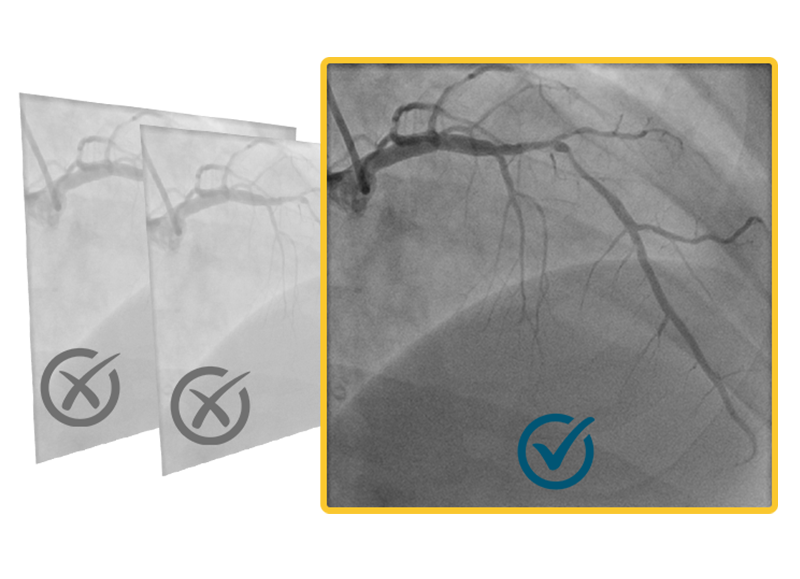

One Angiogram: Simplifying Inputs

FFR results from a single angiogram without wires, drugs, or file management delays.

Powered by a Single Angiogram

Advanced flow + geometry analysis provides accurate FFR of a target vessel from only one angiogram, not two or three